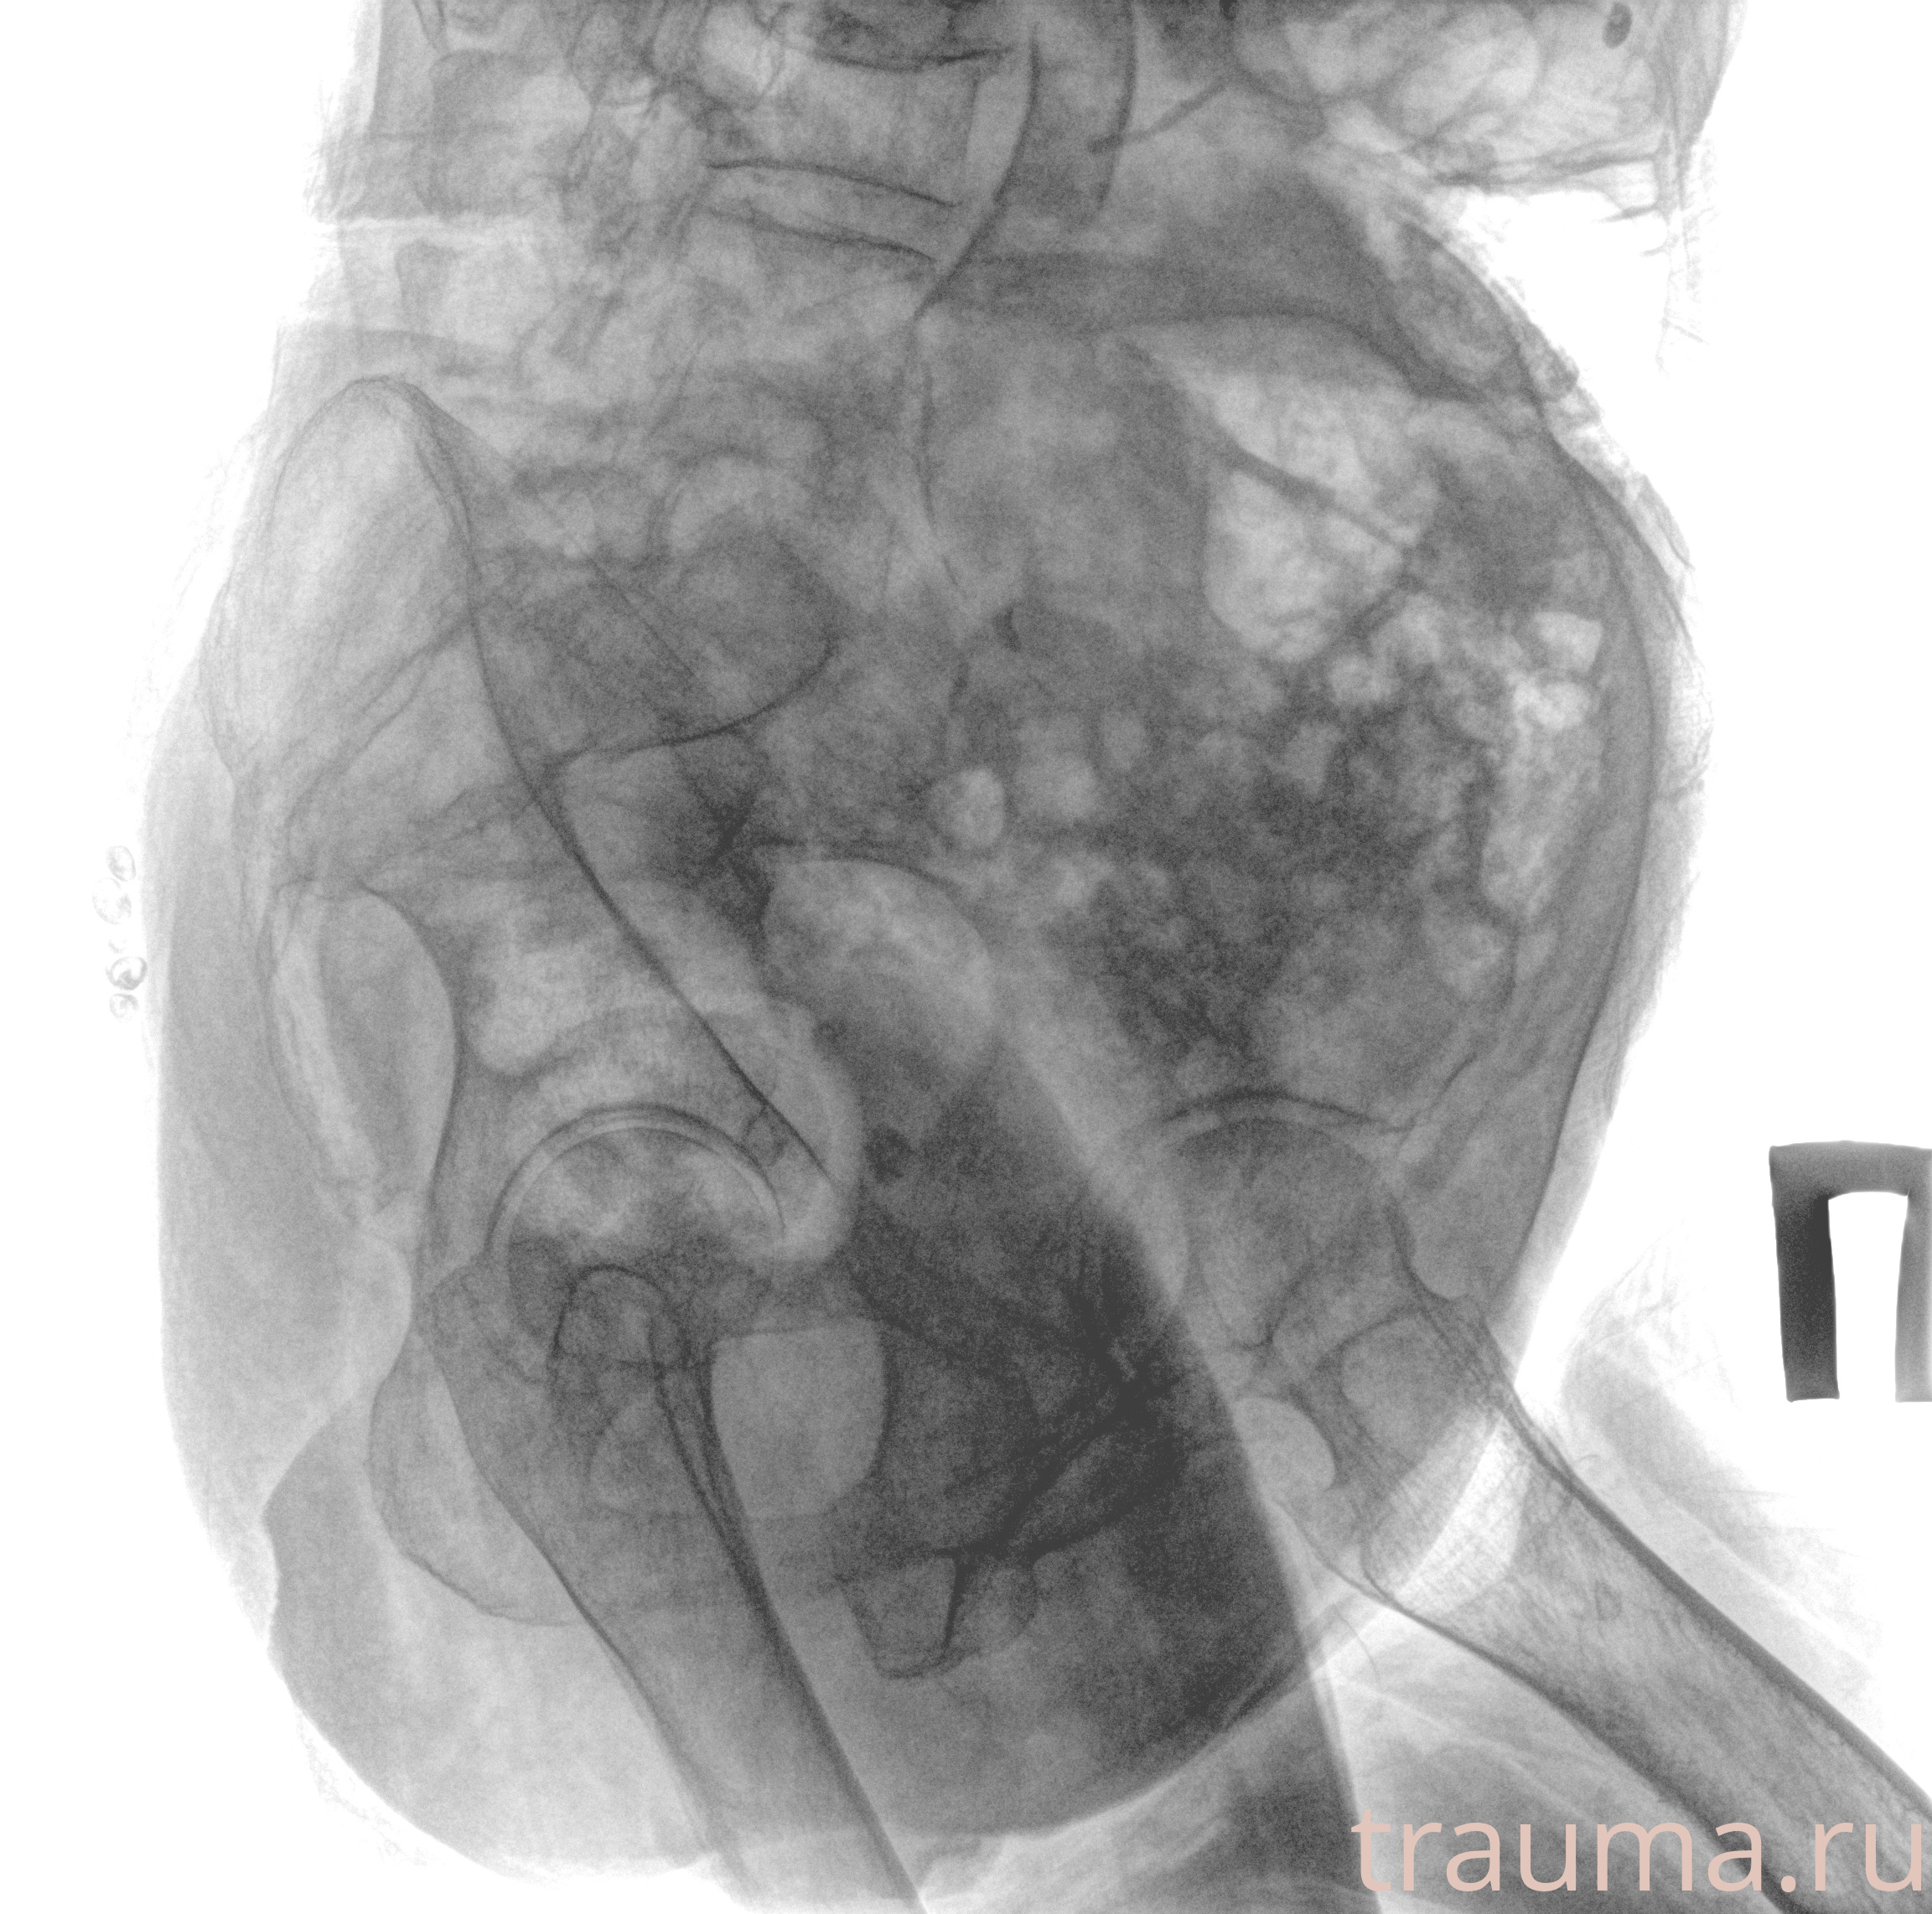

Рентген на дому: по вашему адресу приезжает врач-рентгенолог, травматолог-ортопед с мобильным рентгеновским аппаратом, проводит диагностику травмы или заболевания, делает необходимые рентгенограммы, дает рекомендации по дальнейшему лечению. Получить качественные снимки в домашних условиях возможно благодаря уникальной методике, разработанной МосРентген Центром для института  Склифосовского